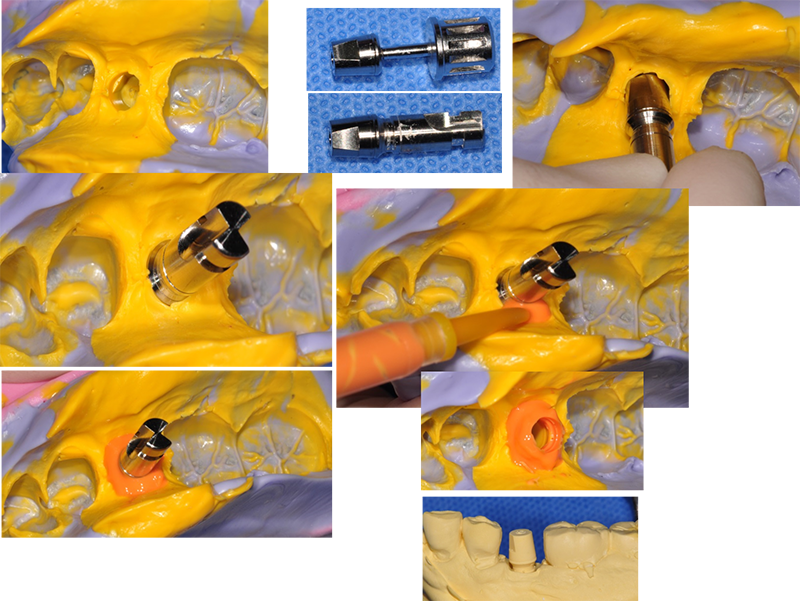

마진을 잘 재현하는 한 가지 tip이다

실린더를 픽업(pick-up)(엄밀한 의미에서는 transfer (트란스퍼))해서 러버 인상체에 ‘재 위치’시킨다.

Polysiloxan light

body impression material를 짜

넣는다. 잇몸에 가려졌던 마진이 재현된다. 임플란트의 구성품들은 각기

동일한 규격을 갖고 있다. 임플란트 보철이 쉬운 이유다.

완성된 석고 모형에서 통법대로 보철물을 만들면 된다.